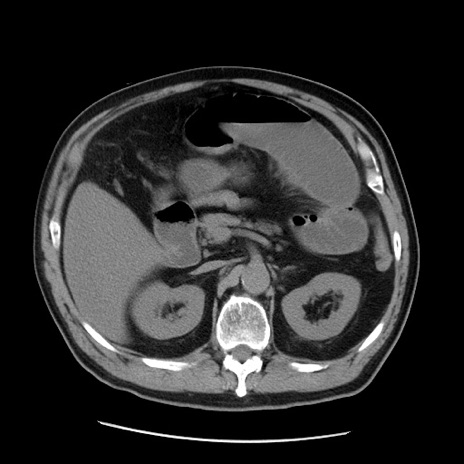

症例20(横断像)

【症例】 60歳代男性

【主訴】 腹部膨満、嘔吐

【現病歴】5日前頃より倦怠感を認め食事量減少し4日前の朝嘔吐、食事摂取困難となった。 3日前近医受診し点滴施行され整腸剤などを処方された。 当日他院を受診し、腹部膨満著明、炎症反応の上昇(CRP10.8、WBC11200)あり、紹介受診となる。

【身体所見】 意識JCS1 受け答えがはっきりしないBP 111/57mHg、 P 67bpm、、BT35.2°C、SpO2 97%(RA)、 腹部:膨隆、打診で鼓音あり、全体的に圧痛有り、腸蠕動音(-)、反跳痛ははっきりせず。

【データ】WBC 11400、CRP 14.20